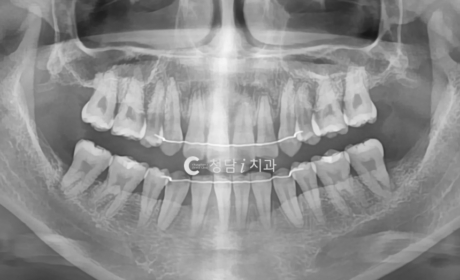

오픈바이트와 삐뚤빼뚤한 치열을 동반한 환자로, 웃을 때 앞니가 닿지 않고 상악 치열이 돌출된 상태였습니다. 정밀 진단 후 하악은 유지하고, 공간 확보와 전치부 배열 개선을 위해 상악 소구치만 발치를 진행하였습니다. 치료 후 앞니가 정상적으로 맞물리며 오픈바이트가 개선되었고, 치열도 가지런해져 심미성과 기능이 함께 회복되었습니다.